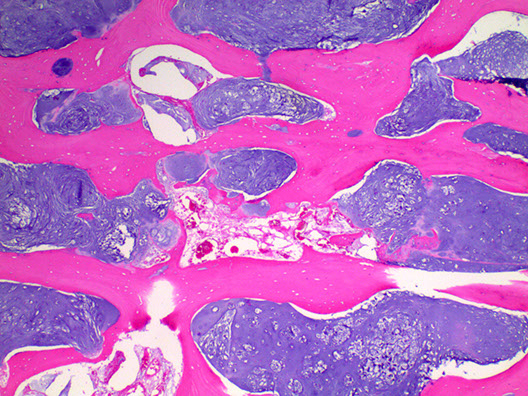

Micro: Islands of cartilage permeating viable lamellar bone; bone made by enchondral ossification

- classified into 3 grades based on cellularity, atypia and pleomorphism

-- most are grades 1 (lobulated; resembles chondroma) or 2 (not lobulated and made of spindle-shaped cells mixed c lacunar cells)

Lobules of hyaline to myxoid cartilage with binucleation, cytologic atypia, increased cellularity

· Grades I (30%): Hyaline cartilage, only mildly atypical

· Grade II (40%): Myxoid change, increased cellularity, atypical

· Grade III (30%): Increased atypia, spindle cell change at periphery of lobules

IHC: (+) S100, D2-40

Chondrosarcoma grade I

Chondrosarcoma Grade II